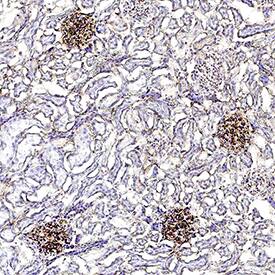

alpha2u-Globulin was detected in immersion fixed paraffin-embedded sections of rat kidney using Mouse Anti-Rat alpha2u-Globulin Biotinylated Monoclonal Antibody (Catalog # BAM586) at 15 µg/mL for 1 hour at room temperature followed by incubation with the Anti-Mouse IgG VisUCyte™ HRP Polymer Antibody (VC001). Before incubation with the primary antibody, tissue was subjected to heat-induced epitope retrieval using Antigen Retrieval Reagent-Basic (CTS013). Tissue was stained using DAB (brown) and counterstained with hematoxylin (blue). Specific staining was localized to glomeruli. Staining was performed using our protocol for IHC Staining with VisUCyte HRP Polymer Detection Reagents.Applications for Rat alpha2u-Globulin Biotinylated Antibody